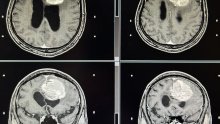

左额叶-胼胝体肿瘤卒中 侵犯对侧额叶 急诊开颅切除 镜下全切

脑血管-烟雾病